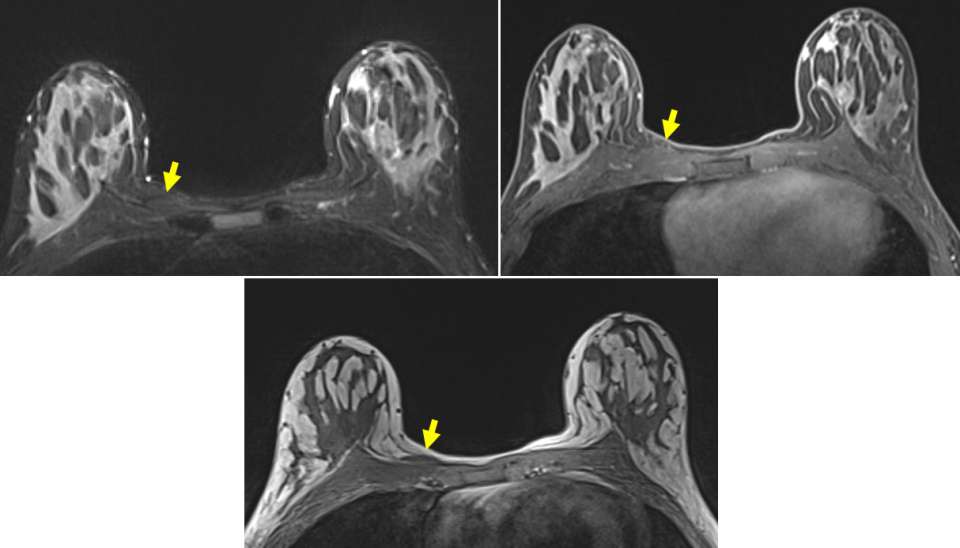

Case: Sternalis Muscle Figure 4

Left T2 STIR: Flat lesion superficial to the right pectoralis major with similar T2 signal compared to skeletal muscle. Right T1 post-contrast: No-contrast enhancement within either the right sternalis or pectoralis muscles. Bottom T1 pre non fatsat: Flat lesion superficial to the pectoralis major with similar T1 signal compared to skeletal muscle.